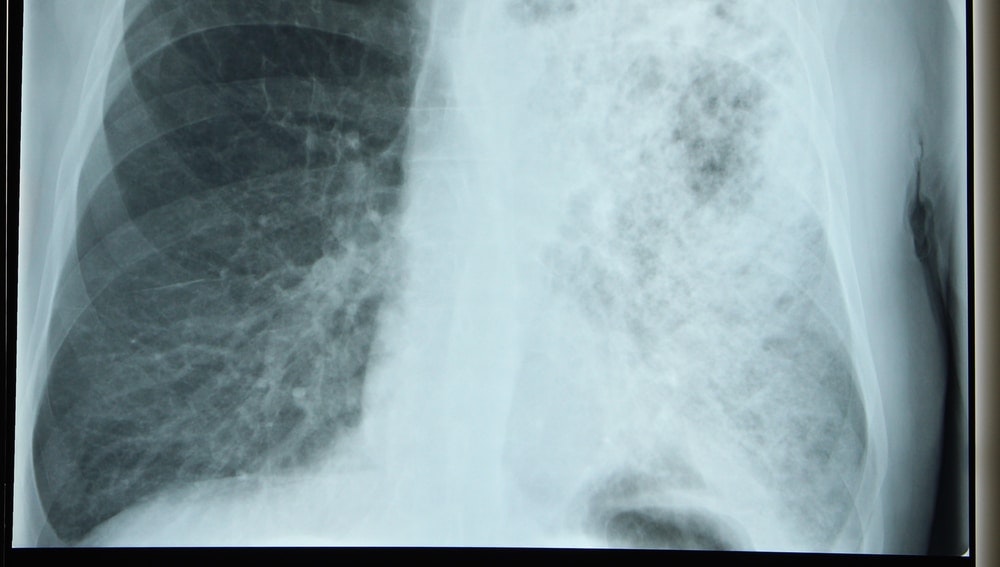

Legionnaires’ disease is a serious type of pneumonia (lung infection) caused by Legionella bacteria, according to the Centers for Disease Control and Prevention (CDC).

Legionnaires’ disease can cause pneumonia symptoms, such as:

- Cough

- Shortness of breath

- Muscle aches

- Headache

- Fever